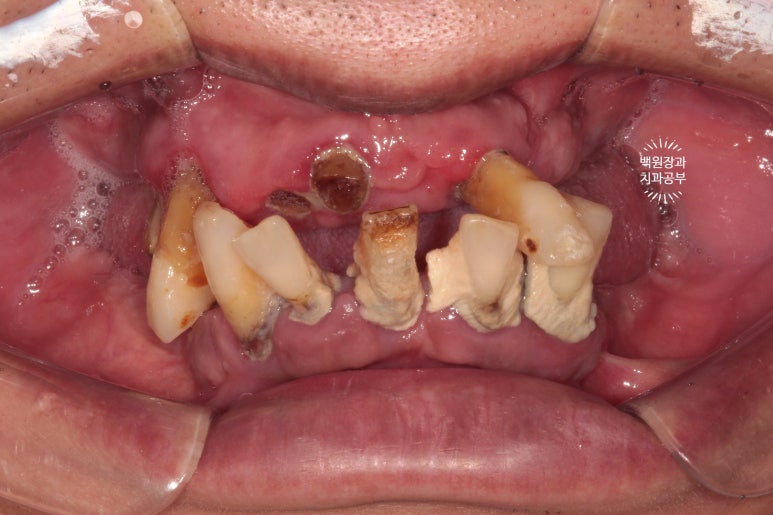

정면에서 본 구강 내 사진입니다.

이미 대부분의 치아들이 자기 자리를 잃어버린 상태였고.... 치석이 너무 많이 침착되어 있었어요..

이것 뭐.. 보나마나 살릴 치아가 없는 상태.